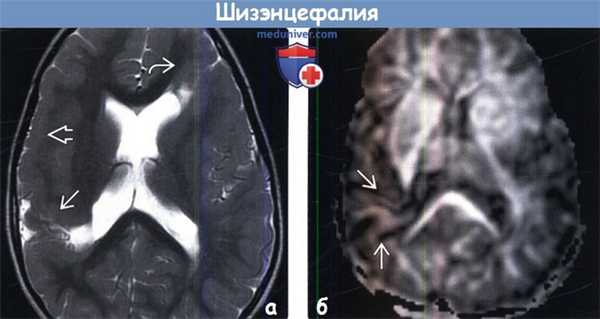

(а) MPT, Т2-ВИ, аксиальный срез: у двухлетнего ребенка с судорожным синдромом и задержкой развития определяются две закрытые шизэнцефалические расщелины: одна расположена в правой теменной доле, другая - в левой лобной доле. Обратите внимание на ассоциированную кортикальную дисплазию: изменения простираются кпереди от правосторонней расщелины вдоль лобной доли.

(б) MPT, DTI, карта фракционной анизотропии: у того же ребенка определяется обрыв трактов белого вещества (БВ) в области расщелины правой теменной доли. Срез данного изображения проходит ниже уровня изменений на изображении слева.